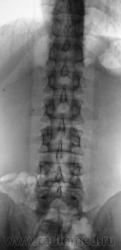

Пациент с болями в пояснице, направлен на рентгенологическое исследование поясничного отдела позвоночника.

задний спондилолистез L3,L4. сакрализация L5.признаки остеохондроза.аномалия тропизма L3-L4 справа ,L5 с обеих сторон.

А позвонков разве не 6? И подготовить бы больного. У нас в поликлинике, почемуто не принято готовить больных к съёмке ПКОП,  только если к ЭУ.

Самый начальный деформирующий спондилоз. Листеза нет. Справа несколько небольших теней, могущих быть кокрементами в мочевых путях...

Ничего, Вы себе не нафантазировали, Игорь Иванович. В данном случае "двуконтурности" заднего края отдельных позвонков не избежать, так как на рентгенограмме в прямой стандартной проекции (снимок выполнен стоя), вроде-бы, как-бы намечается некоторое искривление позвоночника во фронтальной плоскости. Конечно, это никакое не искривление, это просто ротация - 1 - 2 позвонков, и становится понятным, что если 1-2 позвонка чуть ротировались, то на ровность заднего контура всех поясничных позвонков расчитывать не приходится.

О ротации, также свидетельствует различная длина поперечных отростков одноименного позвонка, и это видно.